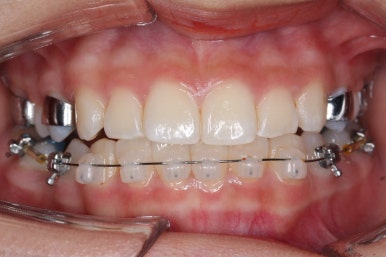

윗니에도 이제 장치를 모두 붙였습니다. 아래쪽은 어느 정도 가지런해지고 나면 부족한 자리를 만들어주기 시작합니다.

부산치아교정잘하는곳 키다리아저씨치과에서 이번 환자분에 사용한 장치는 데이몬 클리어라고 하는 세라믹 자가결찰 장치입니다. 세라믹 자가결찰 장치 중에서 철사를 잡아주는 CAP 부위까지 세라믹으로 되어있어 가장 심미적인 장치라고 볼 수 있습니다.

장치 부착 후 얼굴 모습 보여드리겠습니다.

특히 웃을 때 철사 이외에는 장치가 크게 눈에 띄지 않아서 심미성을 원하시는 분들이 많이 선택을 하는 장치입니다.